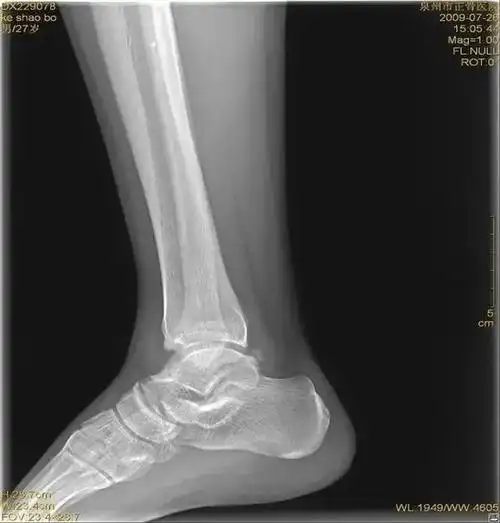

脚踝扭伤一年了,有轻度增生 - 知乎

患者,男,17岁,扭伤致右踝关节肿痛活动受限3天.dr及ct如下

请大家帮看下踝关节扭伤后